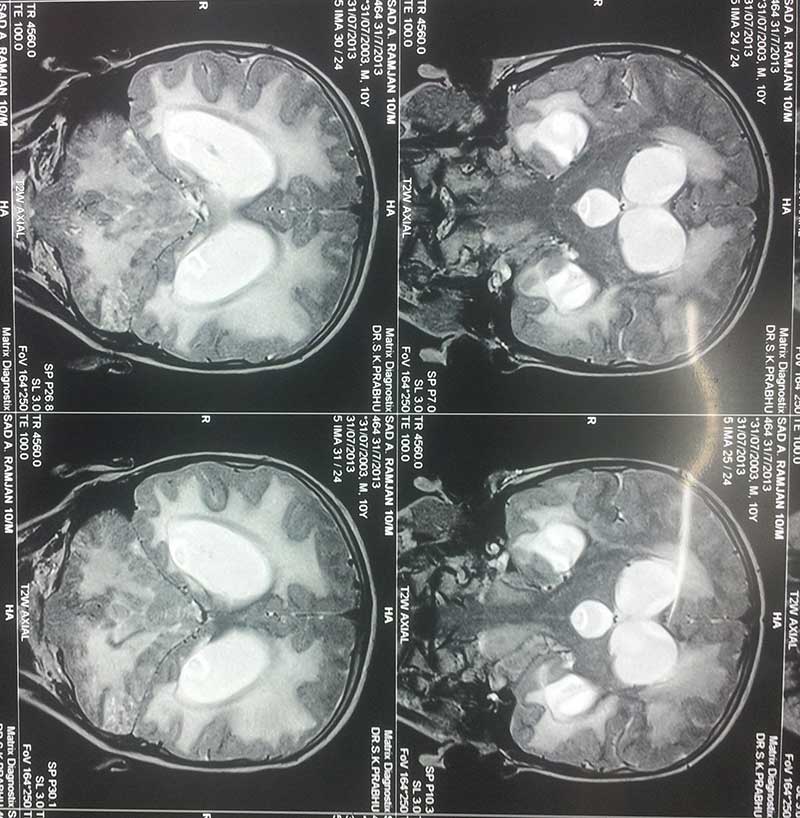

Obstructive Hydrocephalus 2 Pre Op Mri